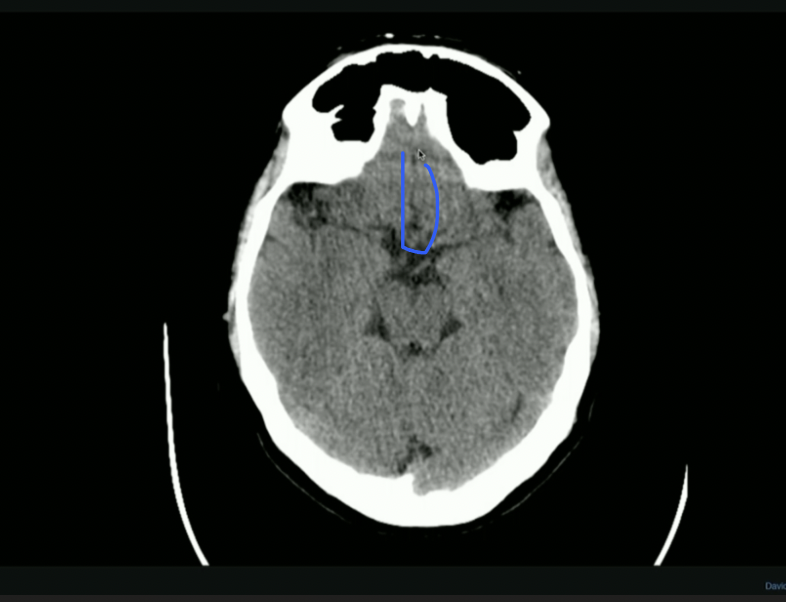

<p>What is the arrow pointing to? + Attachment Points</p>

What is the arrow pointing to? + Attachment Points

• Falx Cerebri

• Anteriorly: Crista Galli on Ethmoid Bone

• Posteriorly: Occipital Protuberance

<ul><li><p>Falx Cerebri</p></li><li><p>Anteriorly: Crista Galli on Ethmoid Bone</p></li><li><p>Posteriorly: Occipital Protuberance</p></li></ul><p></p>